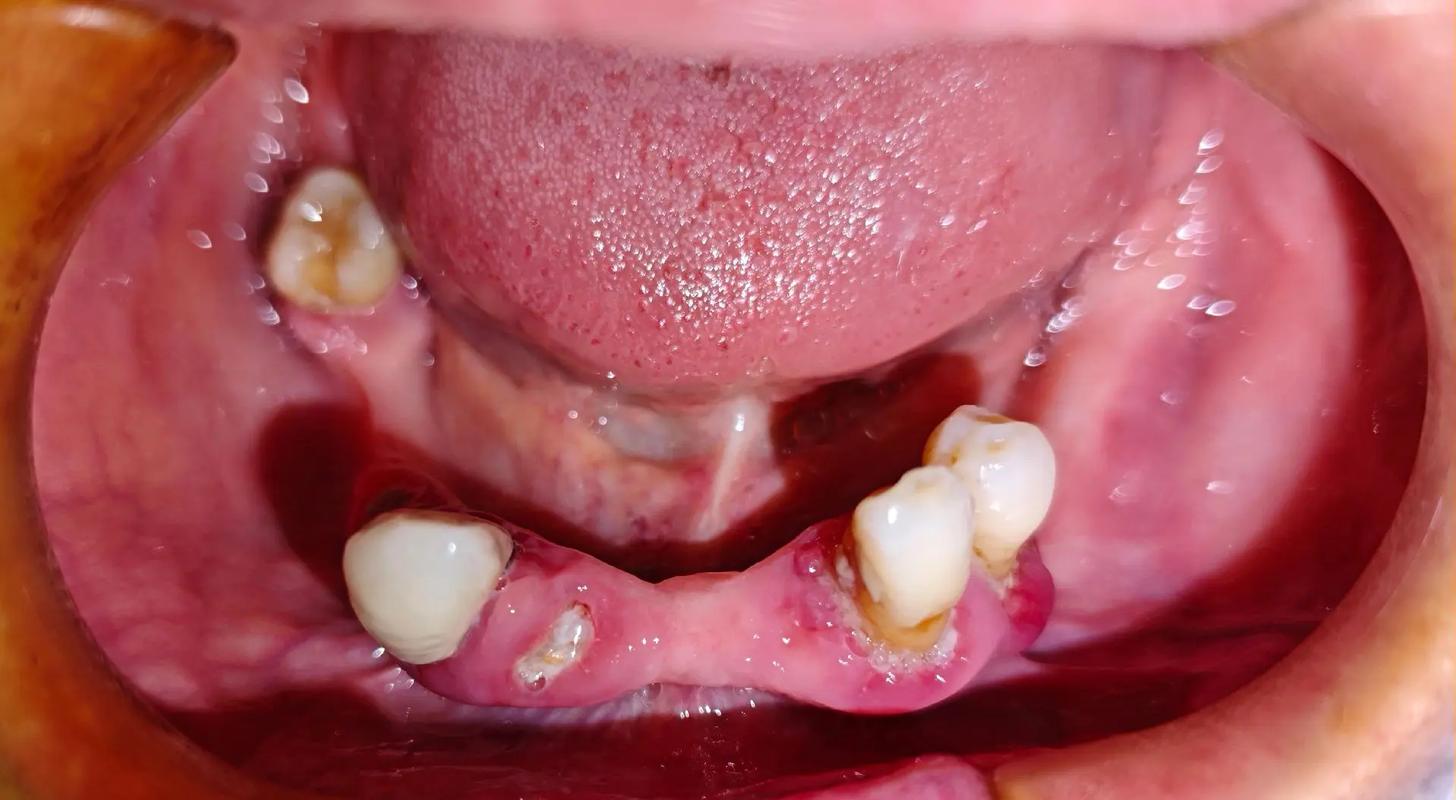

牙周炎患者的口腔环境存在慢性炎症,牙槽骨因炎症持续吸收,可能导致下门牙区骨量不足、骨密度降低,甚至出现骨缺损,若在牙周炎未得到控制的情况下直接种牙,种植体周围可能继发感染,引发种植体周围炎,表现为种植体周围牙龈红肿、溢脓、骨吸收加速,最终导致种植体松动脱落,牙周炎患者种牙的前提是彻底控制牙周炎症,通过系统治疗消除口腔内的感染因素,为种植体创造健康的“生存土壤”。

- 牙槽骨条件差:下前牙区牙槽骨厚度较薄(尤其是唇侧骨板),且骨高度常因牙周炎吸收而不足,易导致种植体初期稳定性不佳或术后唇侧牙龈凹陷。

成功率:若牙周炎控制良好、骨增量成功、患者依从性高,下门牙种植体5年成功率可达90%以上,10年成功率约85%。

- 骨量不足导致修复失败:若术前骨量评估不足,种植体可能因骨吸收而松动,需重新植骨或改用其他修复方式;